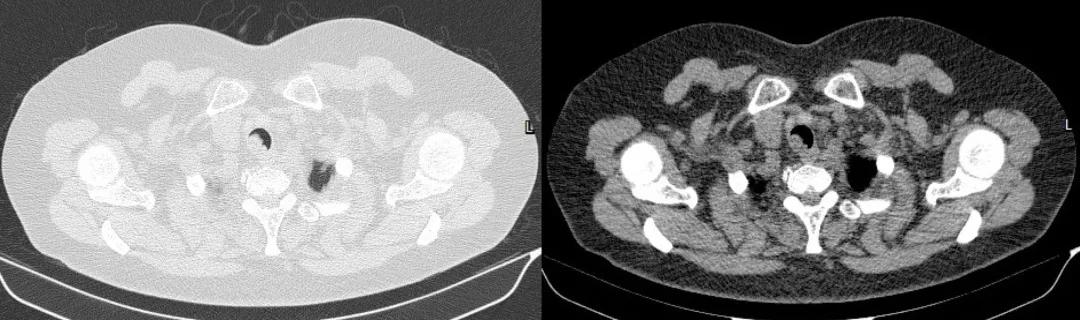

胸部CT:

胸部CT(横截面)

四、影像学检查:表现为气管腔内的软组织密度肿块